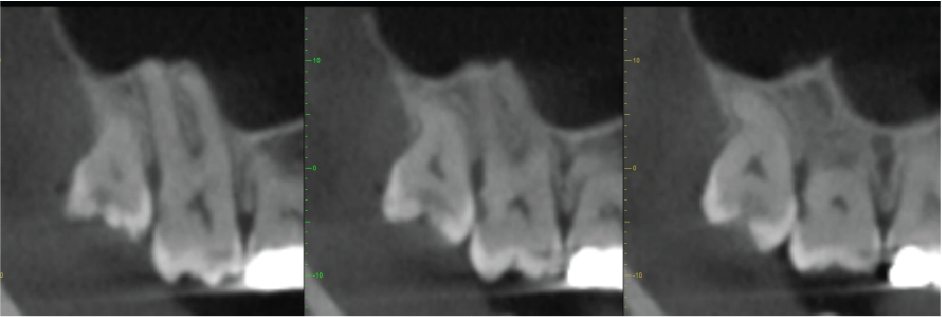

Image 5

Mesio-distal cross-sectional images UR8 and UR7, showing the caries and the distal periodontal bone loss on UR7

Periodontal bone levels are mainly normal or show mild bone loss, but there is greater bone loss associated with UR8 and UR7 and incidental finding of caries. UL4, UL5, UL6 sites have a mature alveolar ridge. No retained roots or bony pathosis. Selected images 3 are bucco-palatal cross-sections across the site. Bone height to the antral floor steadily falls moving distally across the site. There is a short transverse septum at the maxillary antral floor above the palatal side of UL5 site, which should not be relevant to any sinus lift procedure being planned. The alveolar bone quality appears satisfactory, with fairly dense trabeculation and well-defined cortices. The LL6 site has a mature alveolar ridge with no retained roots or bony pathothis. LL7 is mesially inclined, so that its crown overhangs the site. Selected images 4 are bucco-lingual cross-sections across the site. The alveolar ridge has a broad crest. There is a mild lingual undercut, with a lingual concavity present mesially in the site and in the premolar region. The lingual concavity of the submandibular fossa appears towards the distal end of the site. The ID canal is easily identified, lying quite low in the bone. The mental canal is in the plane of LL5. Bone quality is satisfactory, with well-defined thick cortices and fairly evenly trabeculated medullary bone.